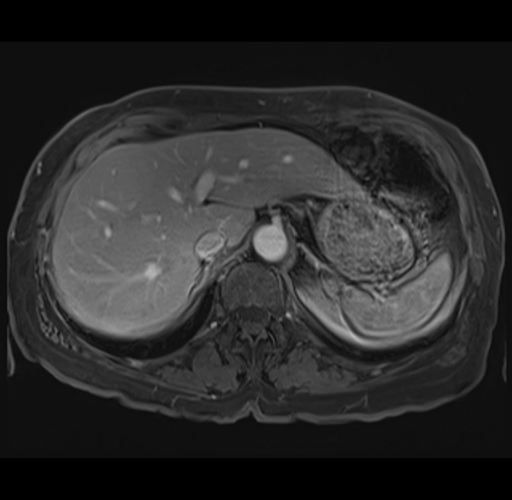

MRI T1